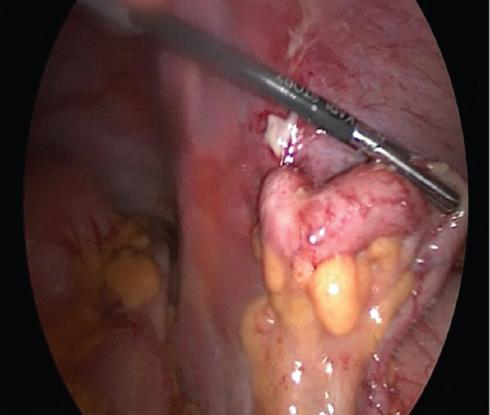

Cirugía realizada: apendicectomía laparoscópica. Abordaje con técnica de Hasson a través de una incisión umbilical de 1 cm, posteriormente se coloca un trocar umbilical de 12 mm y se inicia capnoperitoneo hasta 12 mmHg. Se introduce una lente de 30° y se realiza laparoscopia diagnostica. Se procede a la colocación de trocares de 5 mm, de región suprapúbica y de flanco izquierdo.

Hallazgos: adherencias laxas del epiplón a la pared. Líquido libre purulento de aproximadamente 20 ml. Apéndice vermiforme de 10 cm, hiperémico, edematoso en toda su extensión, con placas fibrinopurulentas. Se realiza apendicectomía y se maneja el muñón con técnica de Halsted. Sin complicaciones, con sangrado mínimo (Figs. 2 and 3).